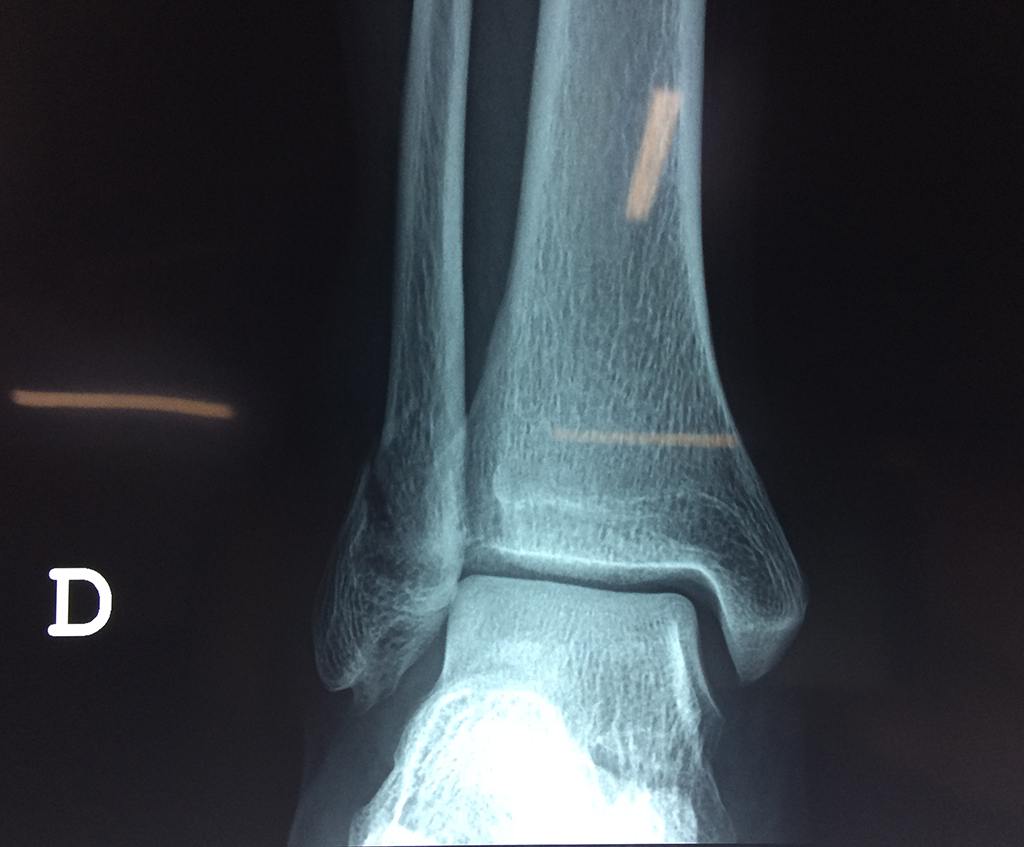

Cuando se necesita cirugía, es probable que esta implique el uso de clavijas de metal, tornillos o placas para sostener los huesos en su lugar mientras la fractura se consolida. Los elementos de soporte pueden ser temporales o permanentes.

- Los extremos de los huesos están desalineados entre sí (desplazados).

- La fractura se extiende hasta la articulación del tobillo (fractura intra-articular).